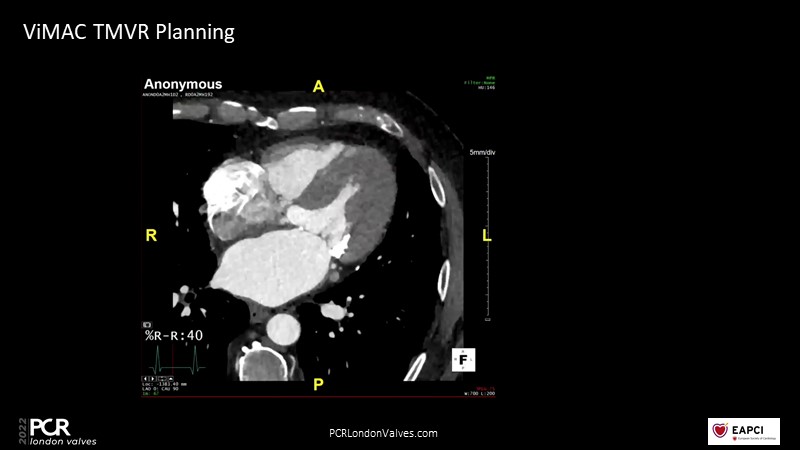

Transcatheter mitral valve replacement - From planning to final assessment

In this session, a panel of experts share their experience with transcatheter mitral valve replacement and more specifically new planning and guidance tools using multiple imaging modalities.

- To leverage CT planning for a better prediction of outcomes in transcatheter mitral valve procedures